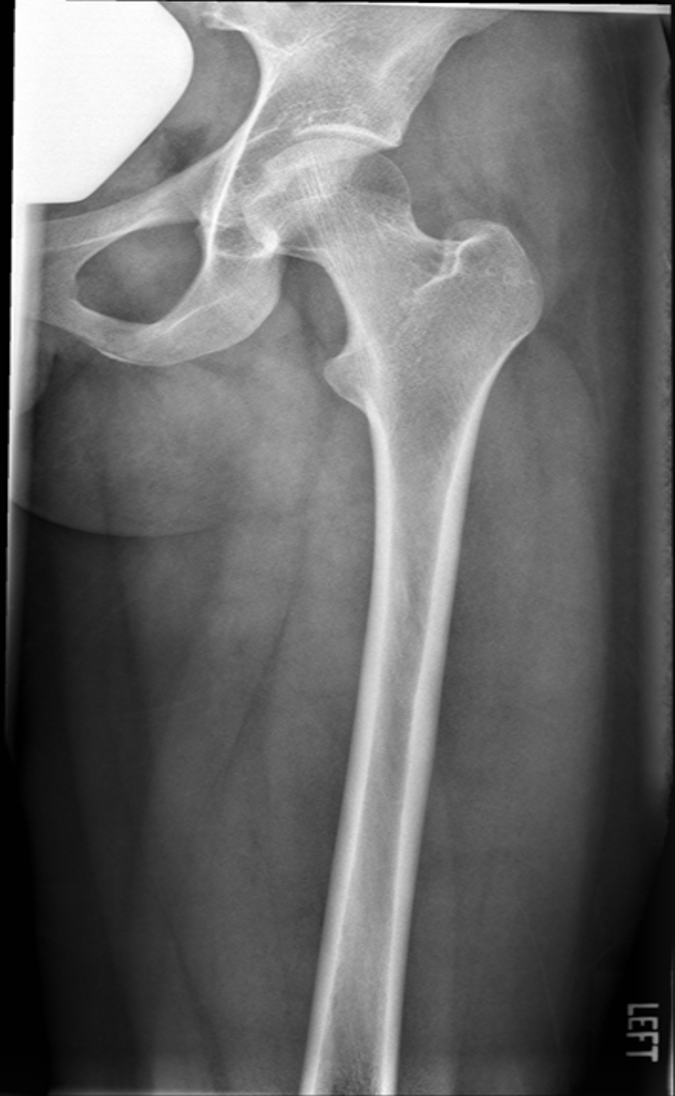

lesser trochanter not seen beyond the medial border of the femur

only very small portion

what is the main critique for an AP femur?

under rotated

what is the image critique of this AP femur?

good image